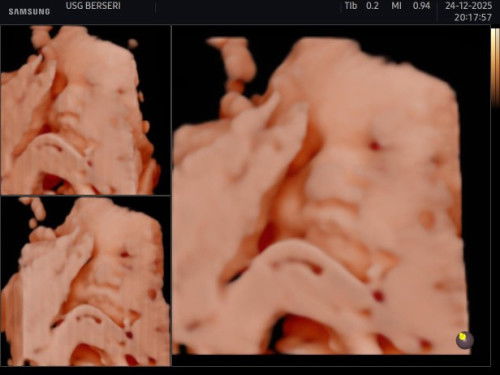

#mohonbantujawabbunda Aku masuk tm 3 bun nih, nah dari tadi siang tuh merasa kek tendangannya kecil tapi kek sakit gitu ngilu beberapa kali sampe malem ini, ditambah mual juga kenapa iya bun?